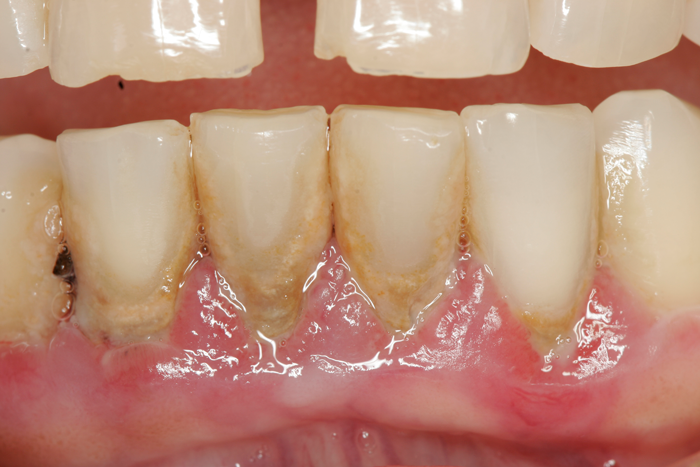

Patient’s teeth on the day of periodontal surgery.